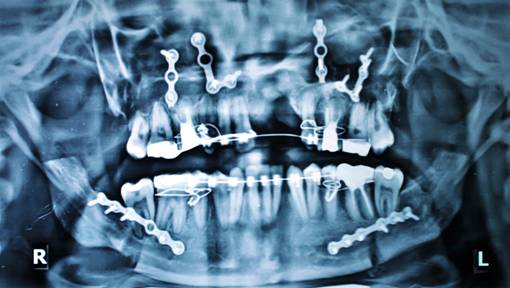

MAXILLARY LEFORT I ADVANCEMENT

BILATERAL SAGITAL SPLIT OSTEOTOMY SETBACK |